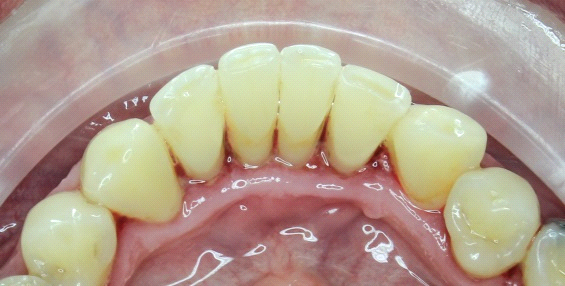

Dentálna hygienička sa potom pustí do čistenia vášho úsmevu. Pomocou ultrazvuku odstráni zubný kameň, ktorý vzniká mineralizovaním zubného povlaku a časom sa môže zmeniť na zubný kaz. Celý proces funguje tak, že ultrazvuk naruší priľnavosť zubného kameňa a ten odpadne. Ak je potrebné odstrániť ho mechanicky, použijú sa škrabky alebo kyrety.

Na odstránenie povlaku a zafarbenia (napr. z kávy, cigariet, jedál…) použije dentálna hygienička kefky, leštiace pasty či “air flow”. Tento prístroj (po slovensky “pieskovač”) krásne vyleští a vyčistí vaše zuby prúdom vzduchu, vody a jemného prášku.